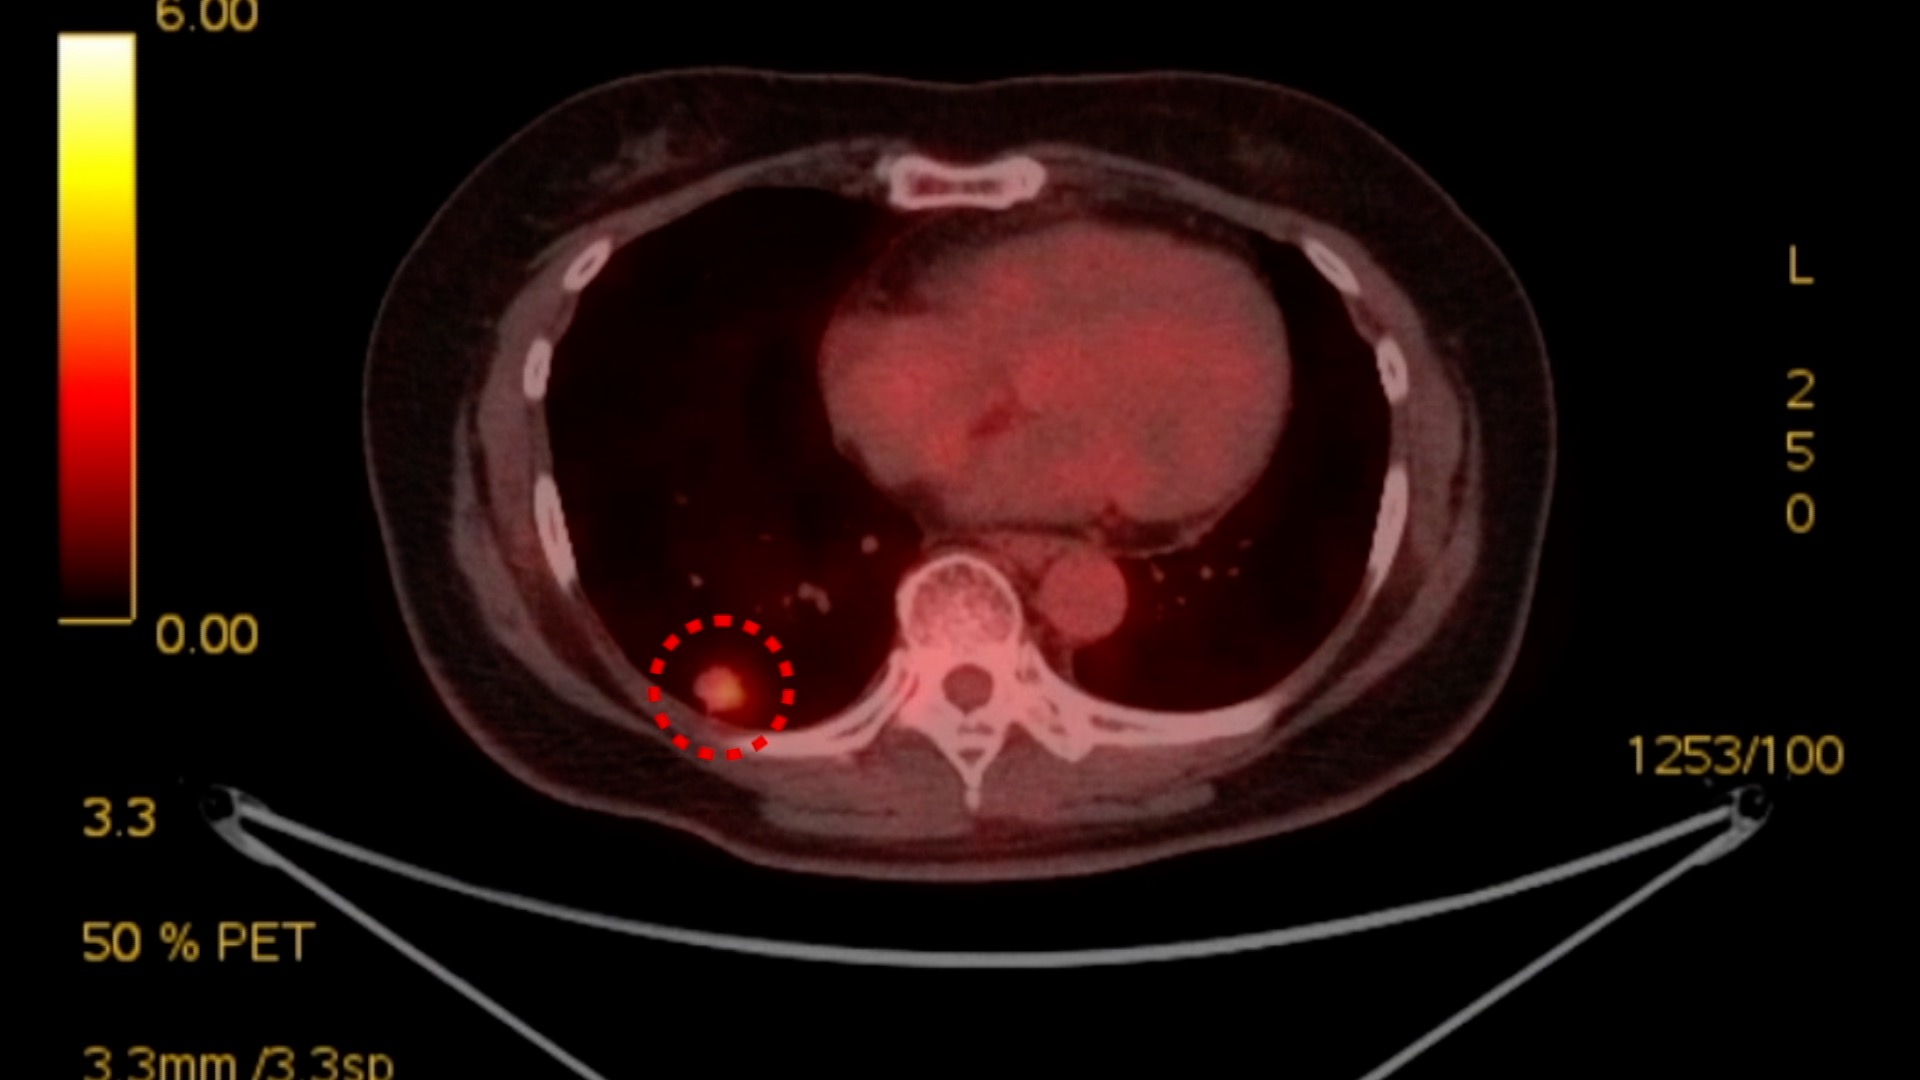

64세 남성은

폐암 3기 진단을 받고 항암 치료에 대한 두려움이 컸습니다.

하지만 그가 받은 면역항암 치료는 기존 항암 치료와 달리 부작용이 거의 없으면서도 효과는 확실했습니다.

4.4cm의 종양을 1.1cm로 줄여 수술로 암을 완전히 제거할 수 있었습니다.